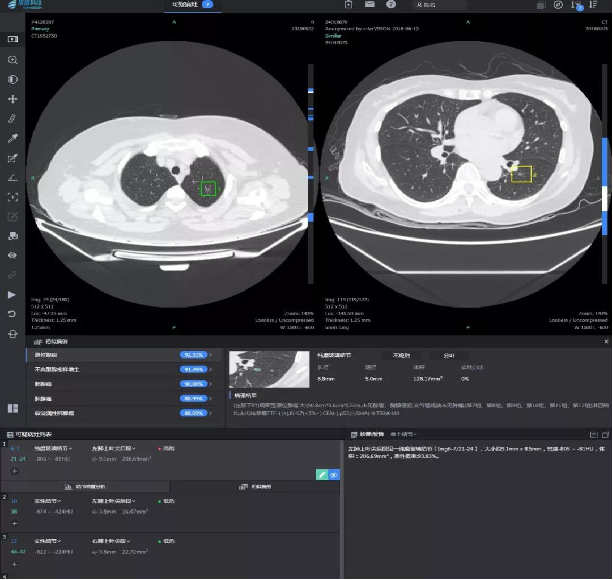

“人工智能(AI)系统可以对每一副图像进行地毯式筛查,避免因为经验差异和医生的视疲劳造成的漏诊。”李美介绍,传统人工筛查需要医生逐个区域用鼠标不停地拖曳、放大,用肉眼一点点甄别影像的每一处可疑部位,一般需要用时3—5分钟,有的疑难的影像片甚至需要更长时间。而人工智能肺小结节筛查系统,基于数十万份高质量胸部CT数据的神经网络深度学习、多维训练,相当于把数十万份由专家诊断的肺小结节大数据植入系统,作为强大支撑作出判断。借助人工智能的力量,系统即能快速对所有完成的胸部低剂量螺旋CT扫描图像进行筛查,并自动对可疑肺小结节进行精准定位,用色框清晰标注小结节坐标提示医生,并对结节的可疑病灶数、性质、直径、体积、CT值等信息以及影像学表现进行描述,医生就可以对这些有问题的地方着重处理。

如图显示,AI软件可以自动识别3mm以上的实性结节、磨玻璃结节(绿方框所示),省去医生寻找的时间

同时,人工智能还能对同一个患者前后做的CT影像检查数据进行对比和分析,不仅大大节省了医生的时间,更可以帮助医生对患者的结节生长速度和动态作出客观的判断,提高诊断的精准率,有助早期诊断和治疗。